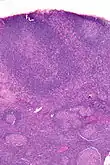

Micrograph showing PTGCs. H&E stain.

Microscopic appearance

PTGCs is characterized by:[1]

- follicular hyperplasia (many follicles),

- focally large germinal centres, with poorly demarcated germinal centre (GC)/mantle zone interfaces (as GCs infiltrated by mantle zone lymphocytes), and

- an expanded mantle zone.